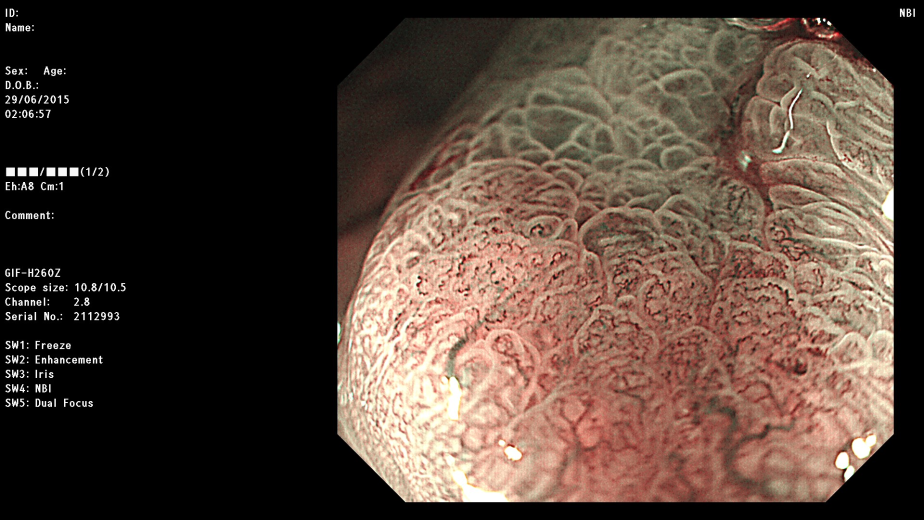

现在,胃镜检查不仅仅是感觉轻松,更主要的是胃镜检查设备的革新和升级,在原本的电子胃镜基础上开展了NBI技术(Narrow Band Imaging,NBI,窄带成像)以及放大染色技术等,医生观察到的胃粘膜是那么的清晰明了,微小至1-2毫米的病灶也逃不出新技术的“火眼金睛”,使得极为隐蔽的毛病,尤其是极早的胃癌都能发现,这才是新一代胃镜的最大价值所在。可以预测,随着胃镜新技术的普及,早期的胃癌都可以发现,也就都可以治愈,胃癌就成为可治愈的癌症之一。发现一例早癌,挽救一个生命,幸福一个家庭,安宁一片天空。

再放大后的观察